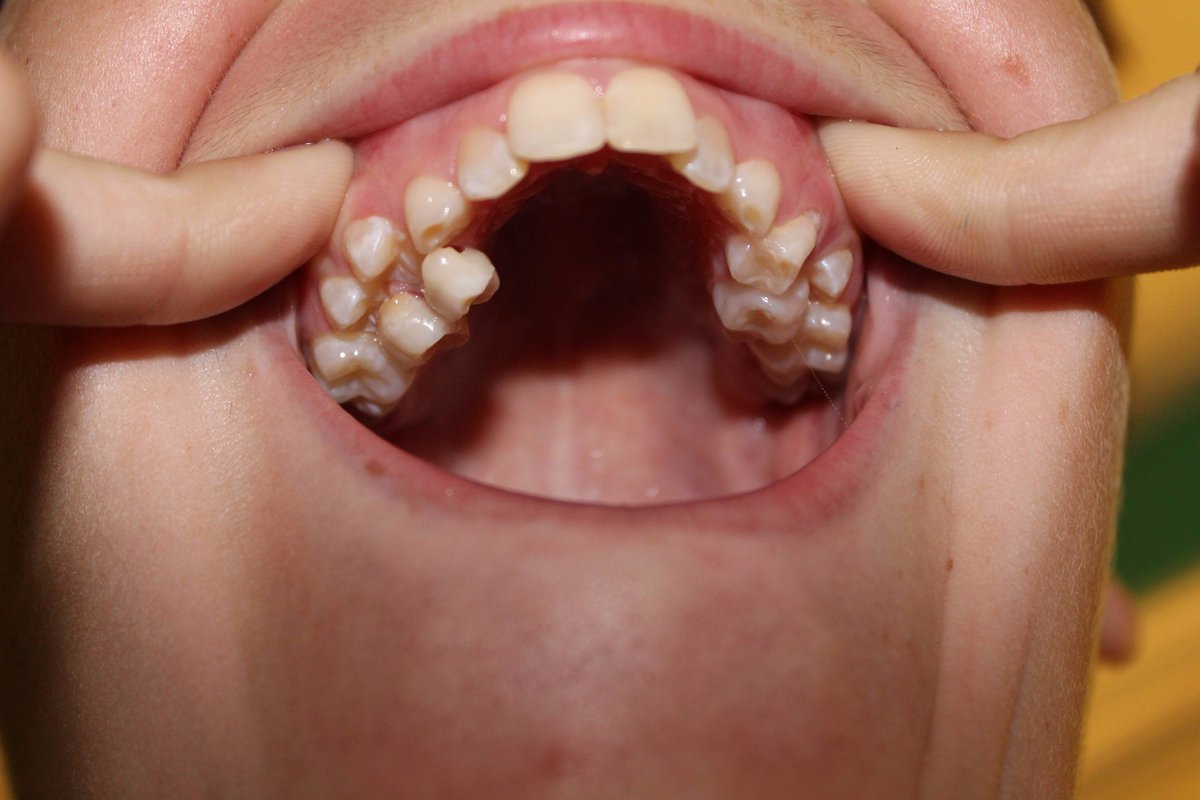

Why Some People Have 32 Teeth And Some Have Just 28 Teeth Chat With

Indian Woman 26 Crowned Guinness World Record Title For Having Most